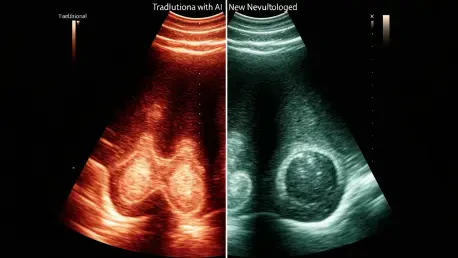

The innovation pioneered by a Johns Hopkins team, led by biomedical and electrical engineer Muyinatu “Bisi” Bell, represents a paradigm shift in how ultrasound data is interpreted. Crucially, the advancement is not in the physical ultrasound machine but in the software that processes the raw data it collects. Traditional ultrasound systems build an image based on the amplitude, or strength, of returning sound waves. Stronger signals create brighter pixels, while weaker ones are darker. This method, however, is highly susceptible to the distortions of acoustic clutter.

In contrast, the Johns Hopkins method is coherence-based. Instead of measuring signal strength, it analyzes the uniformity of the returning sound waves. Signals that reflect off a true anatomical structure are orderly and consistent, or “coherent.” Signals generated by random scatter and clutter are chaotic and “incoherent.” By intelligently filtering out this incoherent noise and focusing only on the unified signals, the new software constructs an image of astonishing clarity, effectively erasing the static that has long clouded diagnostic judgment.